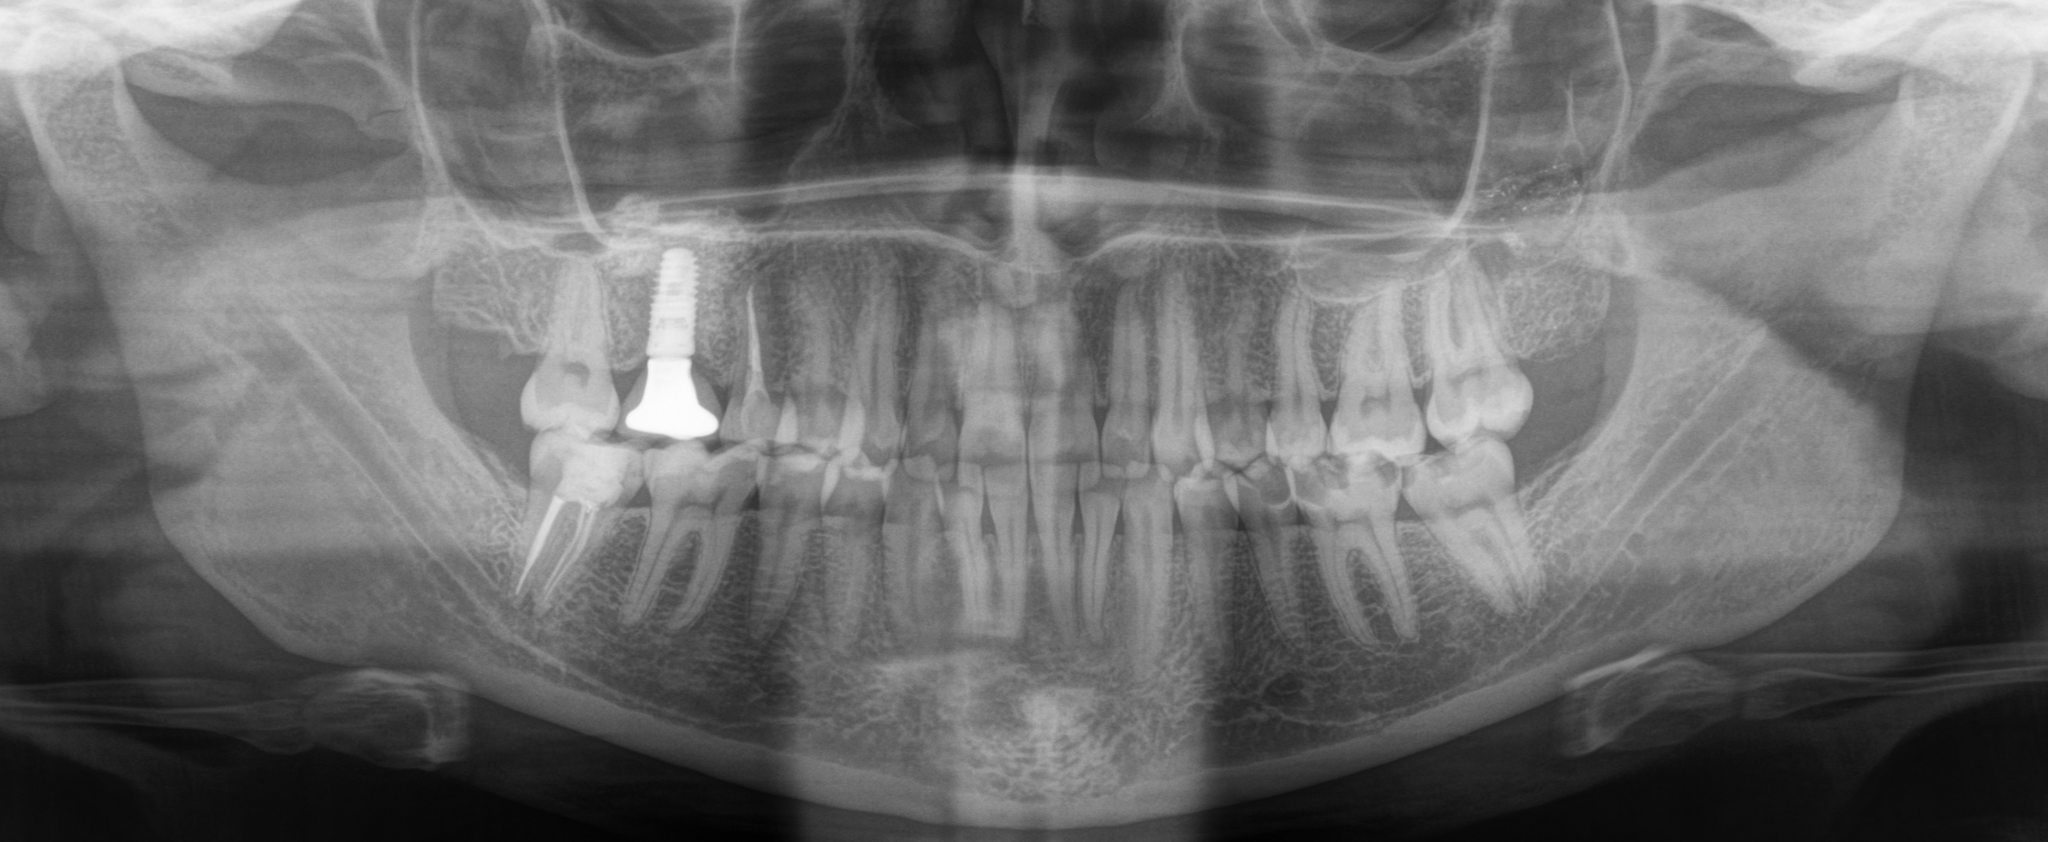

На панорамном снимке, сделанном после имплантации, хорошо видно, насколько высоко и неудачно она располагается:

Вжух и год позади:

В целом, каких-то явных изменений нет. В подтверждение тому, что это не один и тот же снимок, вы можете обратить внимание, что на имплантате уже установлена постоянная коронка.

Добрый вечер… А что это значит?... Прекрасно видно, что фолликулярная киста начала расти и оттеснять зуб мудрости дальше в пазуху, что несколько затрудняет его удаление. Блять, подумал я, надо было сразу удалять.

Контрольный снимок после удаления: